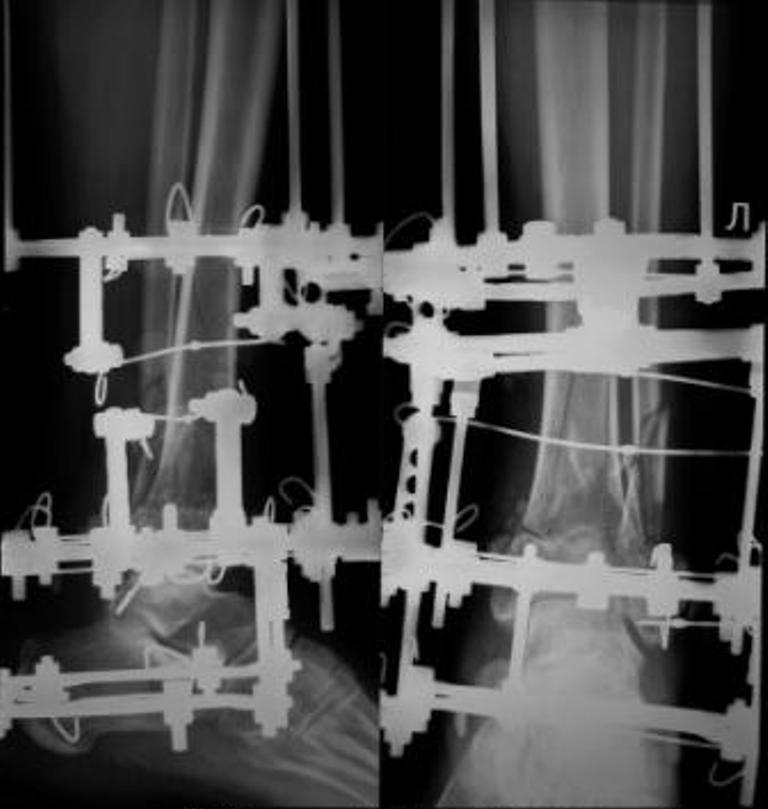

[Ortho] Перелом дистального отдела костей голени

До лечения, в процессе, через 8 мес.